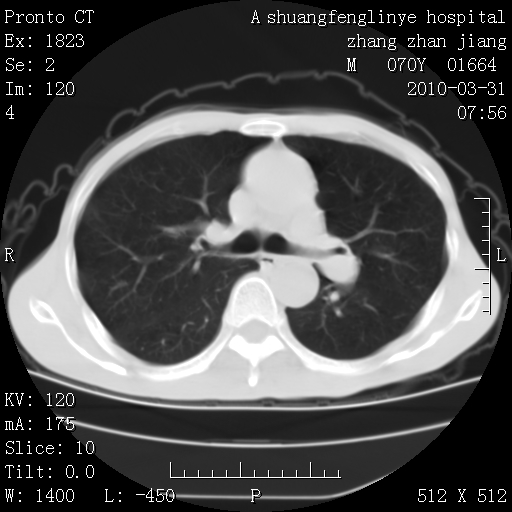

双上肺继发型tb并左上空洞形成,主动脉冠脉钙化。

1)两肺上叶继发性肺结核并左肺上叶空洞形成。2)冠状动脉及主动脉钙化。